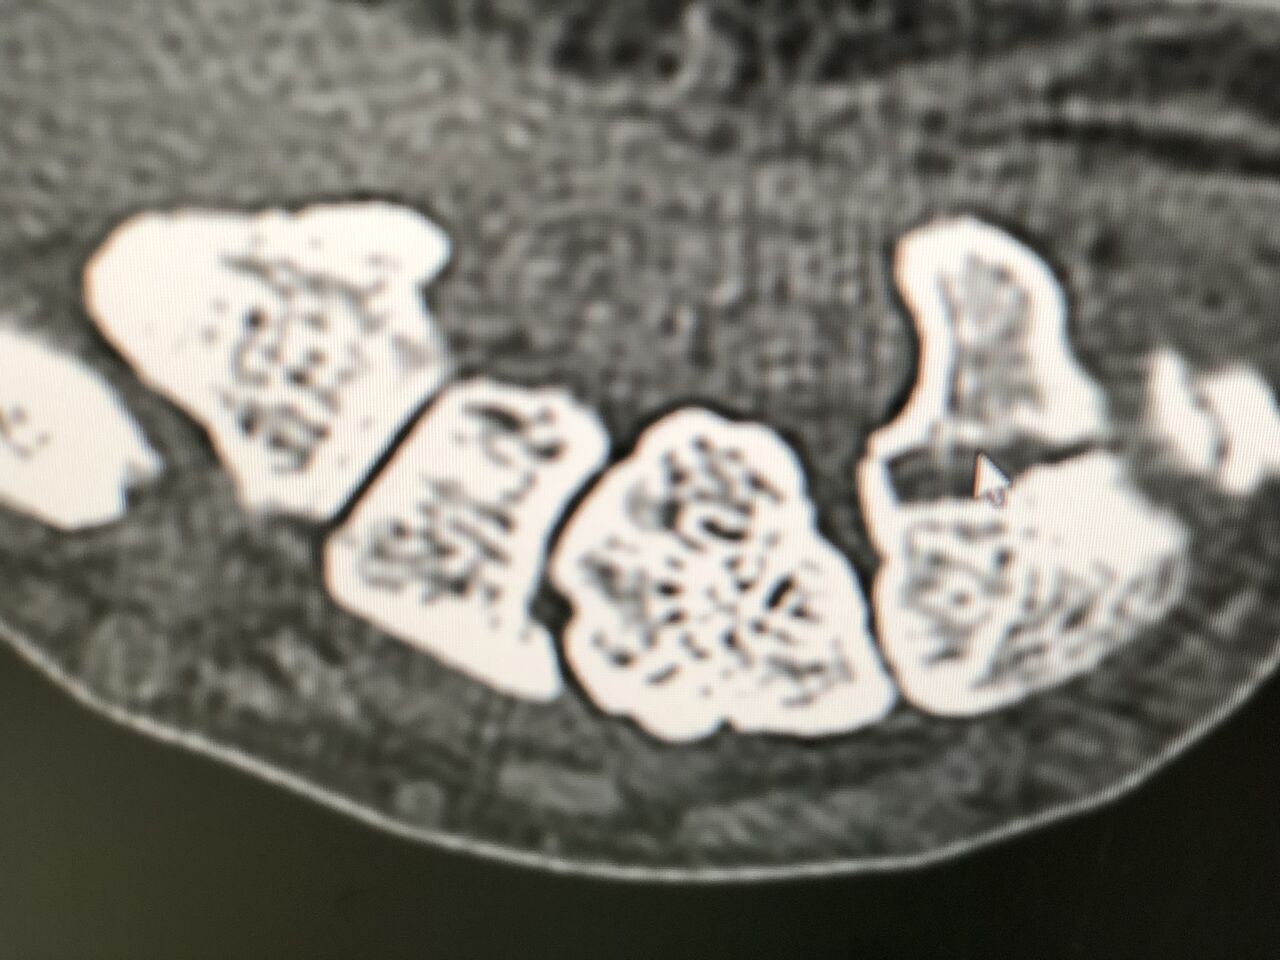

野球アスリートで多い骨折が

この 有鈎骨骨折です

レントゲンでも診断つきますが、

わかりにくいため、CTで精密検査します

ほっておくと、偽関節になり しびれ、

力が入らなくなるため、注意が必要です。

他で、診断つかず

偽関節になって来院されました

6AAF758A-4280-4B98-89C3-FB116E6DC88B

9190420E-589A-4820-9734-CE51A8BB09DA

何とかスポーツ活動できているので、

本人の希望で、

手術も視野にいれ、保存的に治療していきます。